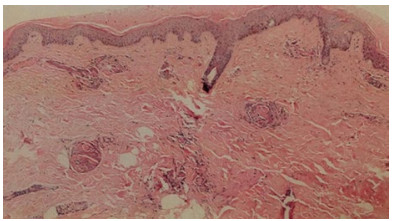

入院后予液体复苏、厄他培南1.0 g/d静脉滴注抗感染、低分子肝素6 000 U/d皮下注射抗凝治疗。查尿常规、病毒核酸五项、胸腹盆腔CT、心脏超声等检查未见明确感染灶,考虑皮肤坏死继发感染不除外。入院第2日将抗生素调整为头孢美唑2.0 g/12 h静脉滴注抗感染治疗。完善相关检查及皮肤病理。患者入院后出现黄疸加重、浓茶色尿、血小板进行性减低、肝脾肿大及腹水,其他化验检查结果:抗凝血酶Ⅲ(AT-Ⅲ)减低,网织红细胞百分比升高、骨髓增生活跃;肝素诱导的血小板减少症(HIT)抗体、活化蛋白C抵抗(APC-R)、抗心磷脂抗体(ACL)、抗β2糖蛋白1(B2GP1)、狼疮抗凝物(LA)、血清免疫固定电泳(IgA+G+M)、血清蛋白电泳均阴性。治疗上予输注血小板,新鲜冰冻血浆改善凝血功能,多烯磷脂酰胆碱、丁二磺酸腺苷蛋氨酸保肝,泼尼松30 mg/d口服控制溶血,补充白蛋白及利尿纠正低蛋白血症、减轻腹水等治疗,患者症状明显好转,血小板维持在50×109/L以上,凝血功能逐渐好转,转氨酶降至正常、胆红素水平逐渐下降,血白蛋白逐渐升高、腹水明显减少。CD55(衰变加速因子)/CD59(反应性溶血膜抑制物)结果回报明显低于正常,将低分子肝素调整为6 000 U/12 h皮下注射加强抗凝治疗。皮肤创面分泌物培养、血培养、腹水培养结果均阴性,继续头孢美唑抗感染治疗,入院第13天患者血常规正常,头面、颈部皮损范围较前缩小。入院第15天皮肤病理回报(图 2),表皮轻度角化过度,棘层萎缩变薄;真皮全层大部分血管内有纤维素样血栓形成,血管周围炎症浸润不明显,符合PF诊断。入院第17天患者体温正常,生命体征平稳。入院28 d患者皮肤出血性坏死明显好转,转至血液科进一步治疗,于3月5日好转出院(图 1)。

| 图 2 本例患者左小腿坏死组织病理(HE×40) |

本例患者,中年男性,急性起病,初始表现为发热、咳嗽、皮疹进行性加重,进而出现大片状皮肤坏死,入院时出现休克、DIC,皮肤病理活检显示真皮全层大部分血管内有纤维素样血栓形成,血管周围炎症浸润不明显,符合PF诊断。患者无明确感染灶,CD55/CD59明显减低,抗凝血酶Ⅲ、蛋白C、蛋白S减低;既往PNH、下肢DVT及门静脉血栓病史,否认家族遗传史,故考虑PNH相关PF诊断。但需与以下疾病鉴别:⑴肝素诱导的血小板减少症(HIT)。HIT是一种免疫介导的疾病,通常发生于肝素治疗后5~10 d,2周后发作不常见。其确定诊断依靠HIT抗体检测,该患者HIT抗体阴性,故可排除该病。⑵华法林诱发的皮肤坏死。华法林治疗早期会诱发蛋白C减少,引起血液短暂性的高凝状态,最终导致广泛性坏死性紫癜。该患者已停用华法林2年,此病可以排除。⑶抗磷脂综合征(APS)。APS是一种自身免疫性多系统疾病,特点是在持续存在抗磷脂抗体的情况下,出现动脉、静脉或小血管血栓栓塞事件和(或)病理妊娠。该患者抗心磷脂抗体(ACL)、抗β2糖蛋白1(β2GP1)阴性;狼疮抗凝物(LA) 1.13(≤1.2)阴性,根据修改版Sapporo标准[14]可排除。⑷血栓性血小板减少性紫癜(TTP)。TTP是一种血管性血友病因子(VWF)裂解酶ADAMTS13活性重度降低引起的血栓性微血管病。其特征为微血管病性溶血性贫血、血小板减少、神经功能异常和肾疾病。皮肤表现多为瘀点或瘀斑,而非皮肤血管发生完全闭塞和损害导致的紫癜。与本病不符。⑸皮肤血管炎。皮肤血管炎可由感染、药物、结缔组织病、恶性肿瘤等多种疾病引起,表现为皮肤瘀点、可触性紫癜、出血性大疱、网状青斑、荨麻疹等,确诊需要通过皮肤活检病理:①纤维素样坏死;②侵入或破坏血管壁的炎性浸润。根据该患者皮肤病理表现可排除该诊断。